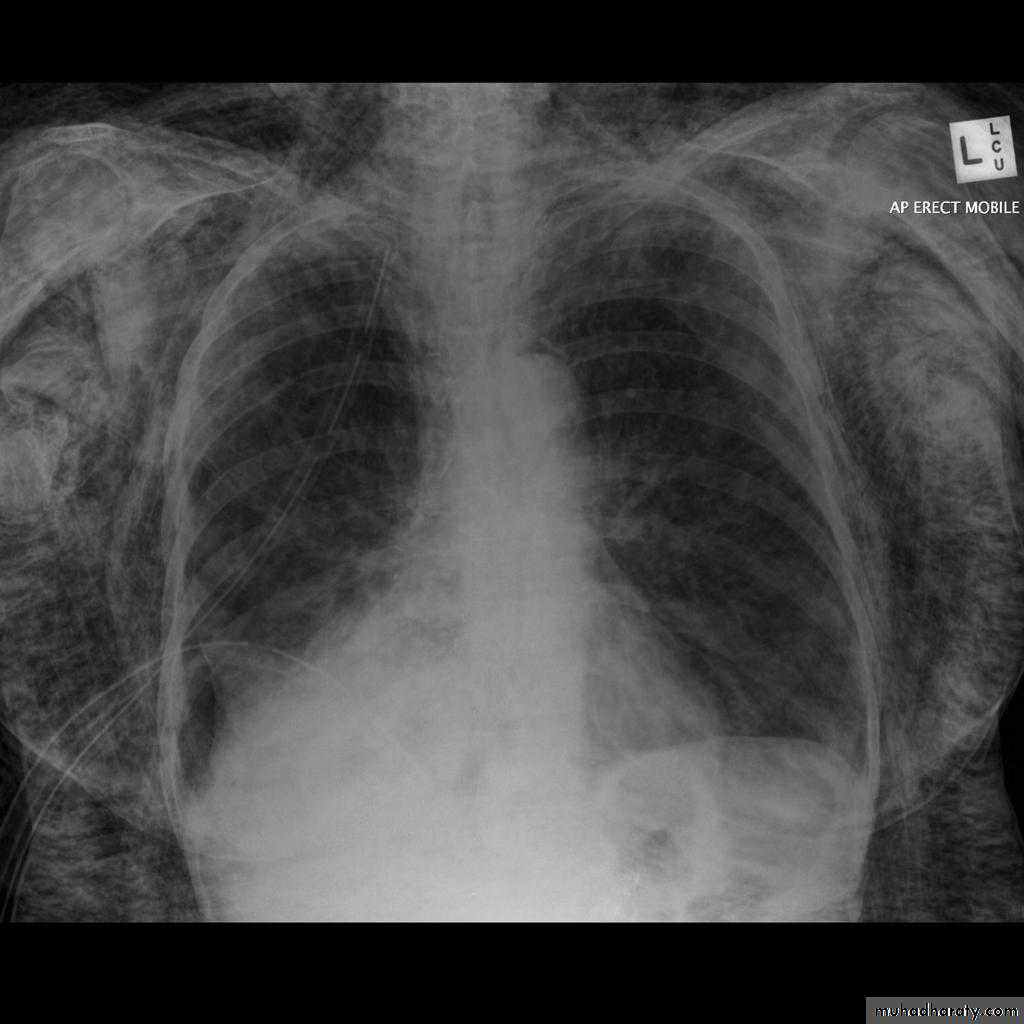

Pleural effusion

Pleural effusion tends to be used as a catch-all term denoting a collection of fluid within the pleural space. This can be further divided into exudates and transudates depending on the biochemical analysis of aspirated pleural fluid. Essentially it represents any pathological process which overwhelms the pleura's ability to reabsorb fluid.Radiographic appearances

Plain radiographChest radiographs are the most commonly used examination to assess for presence of a pleural effusion, however it should be noted that on a routine erect chest x-ray as much as 250-600 ml of fluid is required before it becomes evident 6. A lateral decubitus film is most sensitive, able to identify even a small amount of fluid. At the other extreme, supine films can mask large quantities of fluid.

CXR (erect)

Both PA and AP erect films are insensitive to small amounts of fluid. Features include:

blunting of the costophrenic angle

blunting of the cardiophrenic angle

fluid within the horizontal or oblique fissures

eventually a meniscus will be seen, on frontal films seen laterally and gently sloping medially (note:

with large volume effusions, mediastinal shift occurs away from the effusion (note: if coexistent collapse dominates then mediastinal shift may occur towards the effusion)